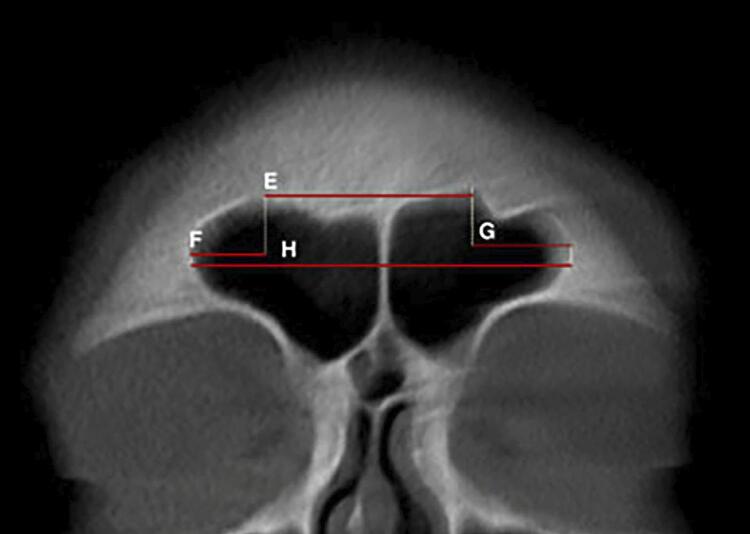

Results: Except for the higher frontal sinus index in females, males exhibited higher numerical values for height, width, and anteroposterior (AP) length. The significance level for all statistical tests was set at 0.05. Multivariate logistic regression identified the following four essential morphometric features: sinus height, anteroposterior length (depth) of the sinus, sinus width, and total sinus width. Both the predictive formula and the ANN demonstrated sexual dimorphism. The accuracy, specificity, sensitivity, precision, and F1- score values were 73.50%, 74.00%, 73.00%, 73.74%, and 73.37% for the regression model, and 76.00%, 84.00%, 68.00%, 80.95%, and 73.91% for the ANN, respectively. Except for sensitivity, the ANN outperformed the predictive formula regarding maximum specificity, accuracy, precision, and F1 score.